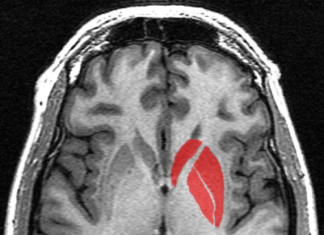

Miniaturized system will treat neurological disorders affecting particular regions in brain

Tiny quantities of medicines as small as 1 cubic millimetre will be transferred to the specific region of the brain circuit without disrupting the...